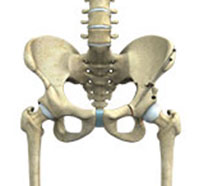

The hip joint is the largest weight-bearing joint in the human body. It is also referred to as a ball and socket joint and is surrounded by muscles, ligaments, and tendons. The thigh bone or femur and the pelvis join to form the hip joint.

The hip joint is a "ball and socket" joint. The "ball" is the head of the femur or thigh bone, and the "socket" is the cup-shaped acetabulum. The joint surface is covered by a smooth articular surface that allows pain-free movement in the joint.

The hip joint is one of the largest weight-bearing joints in the body, formed by the thigh bone or femur and the acetabulum of the pelvis. It is a ball and socket joint with the head of the femur as the ball and the pelvic acetabulum forming the socket.